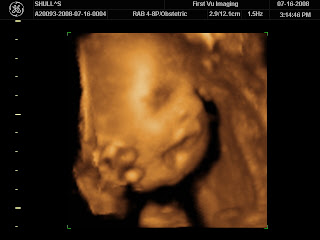

Look at our baby!

Thanks to Andrea, Andrew and I went to have 4-D photos taken of our baby. It was such a fun experience. The technician was careful to only snap photos from the waist up so that we didn’t find out the gender. The baby behaved very well during the session. It had a fascination with one of its feet. It had the little foot all the way up by the head playing with it and wiggling it around. It’s hard to believe that in 2 months, this precious little baby will be at home with us.